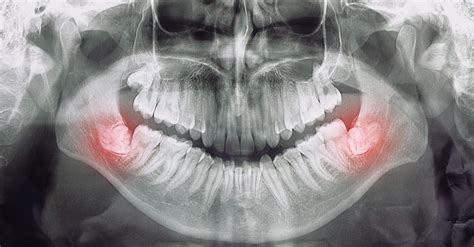

- Diente retenido o impactado: Ocurre cuando un diente no puede emerger completamente porque encuentra un obstáculo o falta de espacio.

La pérdida ósea del hueso alveolar tanto de la mandíbula como del maxilar superior es una consecuencia común de la periodontitis crónica y de la pérdida de dientes. El hueso alveolar forma las crestas en las que están incrustados los dientes.

La causa más común de pérdida ósea es la pérdida de dientes que no se reemplazan, especialmente cuando son varios dientes seguidos. El hueso de los maxilares se conserva mediante la presión y el estímulo de masticar. Cuando se extraen dientes, el hueso se reabsorbe.

Cuando los huesos pierden densidad, se vuelven más porosos. La baja densidad del hueso alveolar se puede detectar con anticipación mediante la captura de imágenes 3D con los escáneres CT de haz cónico. Cuanto más blanco es el color del hueso en la radiografía, más denso es.